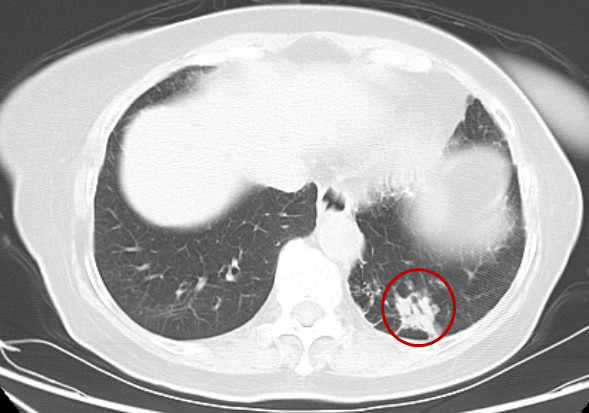

前段时间,赵奶奶在体检时发现左肺部有一个约3厘米大小的结节,确诊为左肺下叶腺癌。“辗转了几家医院,也做了基因检测,但没有找到靶向药物,又怕老人的身体受不了化疗,但保守治疗我们从情感上也无法接受,当时真的难以抉择。”刘女士表示。

周亚夫主任提醒,赵奶奶由于坚持常规体检,肺癌发现得早,没有发现转移(淋巴结处需待术后病理检查),而肺癌的早期诊断对疾病的愈后十分重要,目前最有效的肺癌筛查方法是低剂量螺旋CT,定期的体检应重视,体检发现肺结节,要及时到专科医生处做进一步诊断治疗。(院办 吴靖 胸外二科 陈辉国)